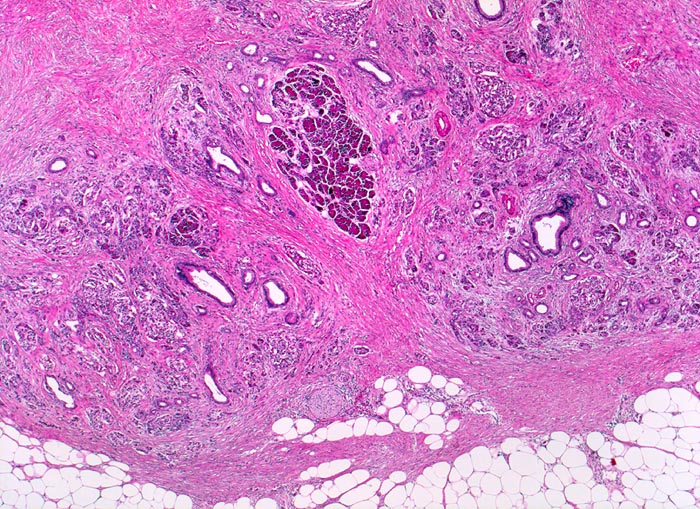

Chronisch-sklerosierende Pankreatitis

In der Übersicht ist die lobuläre Architektur des Pankreas erkennbar. Azini gruppieren sich um intralobuläre Gänge. Das Pankreasparenchym ist aufgesplittert durch eine dissoziierende Fibrose zwischen und innerhalb der Lobuli. Die Entzündung ist minimal ausgeprägt. Die Veränderungen sind herdförmig unterschiedlich schwer. Ein Lobulus scheint weitgehend unbehelligt. Zusammensinterung und Proliferation der inter- und intralobulären Duktuli.

Alkoholiker mit rezidivierten akuten Pankreatitisschüben. Chronische Diarrhoe.

Histologie

Vergrösserung